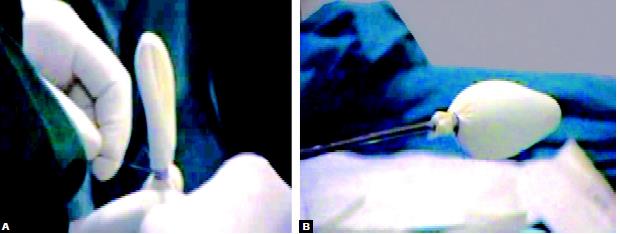

A balloon dissector should be introduced with telescope and balloon is inflated for further dissection of the preperitoneal space. An 11 mm port is introduced without its sharp tip with a laparoscope at 30°. A small preperitoneal pocket is created by manipulating a laparoscope in a sweeping manner. If the balloon dissector is not available the glove finger can be tied around the suction irrigation instrument and can be used to create some preperitoneal space.

Making balloon dissection with the finger of gloves